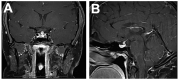

Inflammatory disease of the pituitary gland is known as hypophysitis. There are multiple histological subtypes, the most common being lymphocytic, and the pathogenesis is variable and diverse. Hypophysitis can be primary and idiopathic or autoimmune related, or secondary to local lesions, systemic disease, medications, and more. Although hypophysitis was previously accepted as an exceedingly rare diagnosis, a greater understanding of the disease process and new insights into possible etiologic sources have contributed to an increased frequency of recognition. This review provides an overview of hypophysitis, its causes, and detection strategies and management.